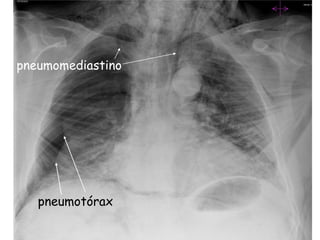

- Perfuração esofágica

Iatrogénica, complicação de cirurgia cervical, sindrome de Boerhaave

(perfuração esofágica espontânea pelo esforço do vómito);

(sind. Mallory-Weiss – laceração da mucosa junção           esofagogástrica   com

hematemese, sem dor)

Dor, vómito, hematemese, febre, enfisema               subcutâneo,     enfisema

mediastínico, timpanismo ou macicez torácica.

Local da perfuração: cervical, torácica e abdominal.

Rx tórax

Trânsito esofágico com gastrografina se perfuração baixa, peritoneal;

com produto não iónico se suspeita de perfuração alta

(gastrografina causa pneumonite por edema pulmonar).

78 a. sexo masc. (PU.19290101055) Abril07

Disfagia intermitente prévia

2 dias com impactação alimentar

Extracção camarões impactados no 1/3 distal esófago

Súbita dispneia, dor torácica

Enfisema cervical e facial após alguns minutos

Polipneia e agitação

Hipóxia com 80% sat

Trânsito com contraste não iónico

pneumomediastino

pneumotórax

Perfuração do esófago

com impactação          Rafia da mucosa +

Esofagocardiomiotomia

Patch do fundo gástrico

com hemivalva anterior

tipo Dor

Patch de Thal